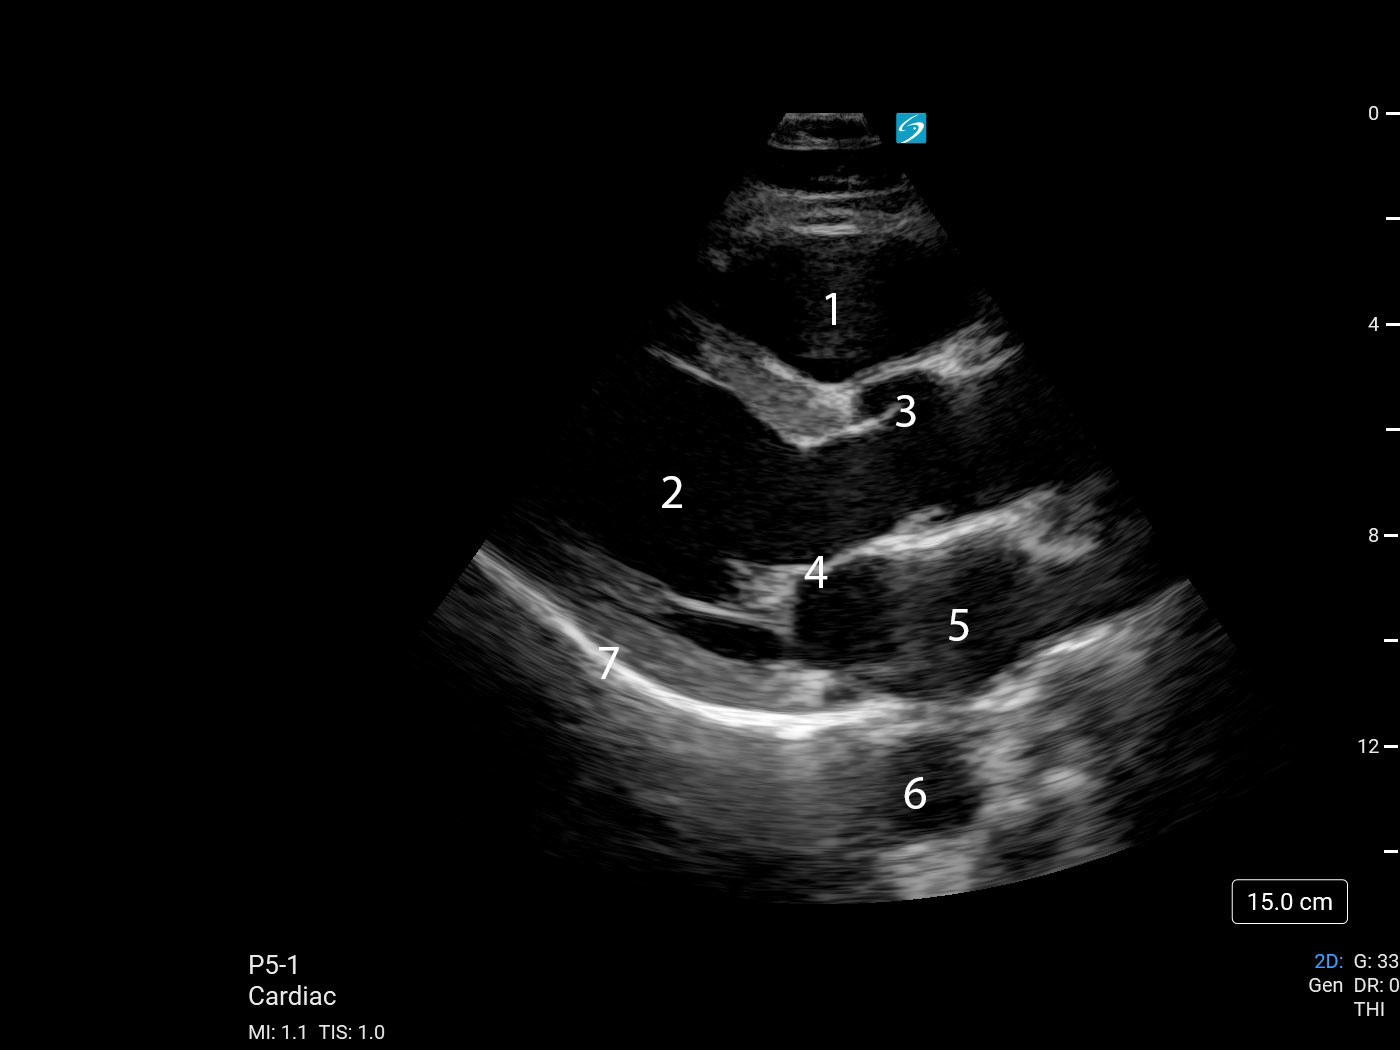

Heart Parasternal Long Axis (PLAX) (Sonosite PX P5-1) 3 Image

1. Right Ventricular Outflow Tract (RVOT)

2. Left Ventricle (LV)

3. Aortic Valve (AV)

4. Mitral Valve (MV)

5. Left Atrium (LA)

6. Descending Thoracic Aorta (DTA)

7. Pericardium